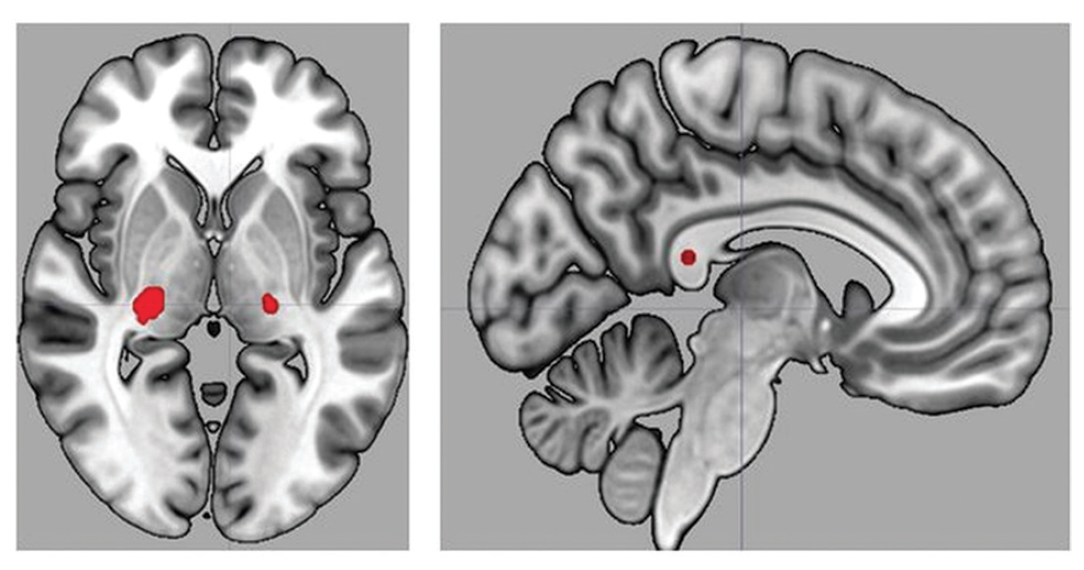

Учитывая ранее установленный факт смещения тканей головного мозга ввиду пребывания на МКС, ученые провели анализ локального смещения тканей мозга в участке интерфейса между мозгом и спинномозговой жидкостью. У космонавтов, которые подвергались длительным космическим полетам, были отмечены значительные локальные изменения в структуре мозга (снимок ниже).

Мозги на Марсе: как космические перелеты влияют на когнитивные функции - 5

Изображение №2: МРТ снимок мозга астронавта, показывающий наличие скопления красноречивых тканей мозга в области вертекса (красный цвет) и локального смещения тканей (синий цвет).

Во время исследования наблюдалась скученность паренхимальных* тканей головного мозга в макушке, которая сопровождалась скученностью моторных, премоторных и первичных сенсомоторных областей. Также было выявлено смещение тканей мозга вдоль краев желудочка, что соответствует предыдущим наблюдениям касательно увеличения желудочков.